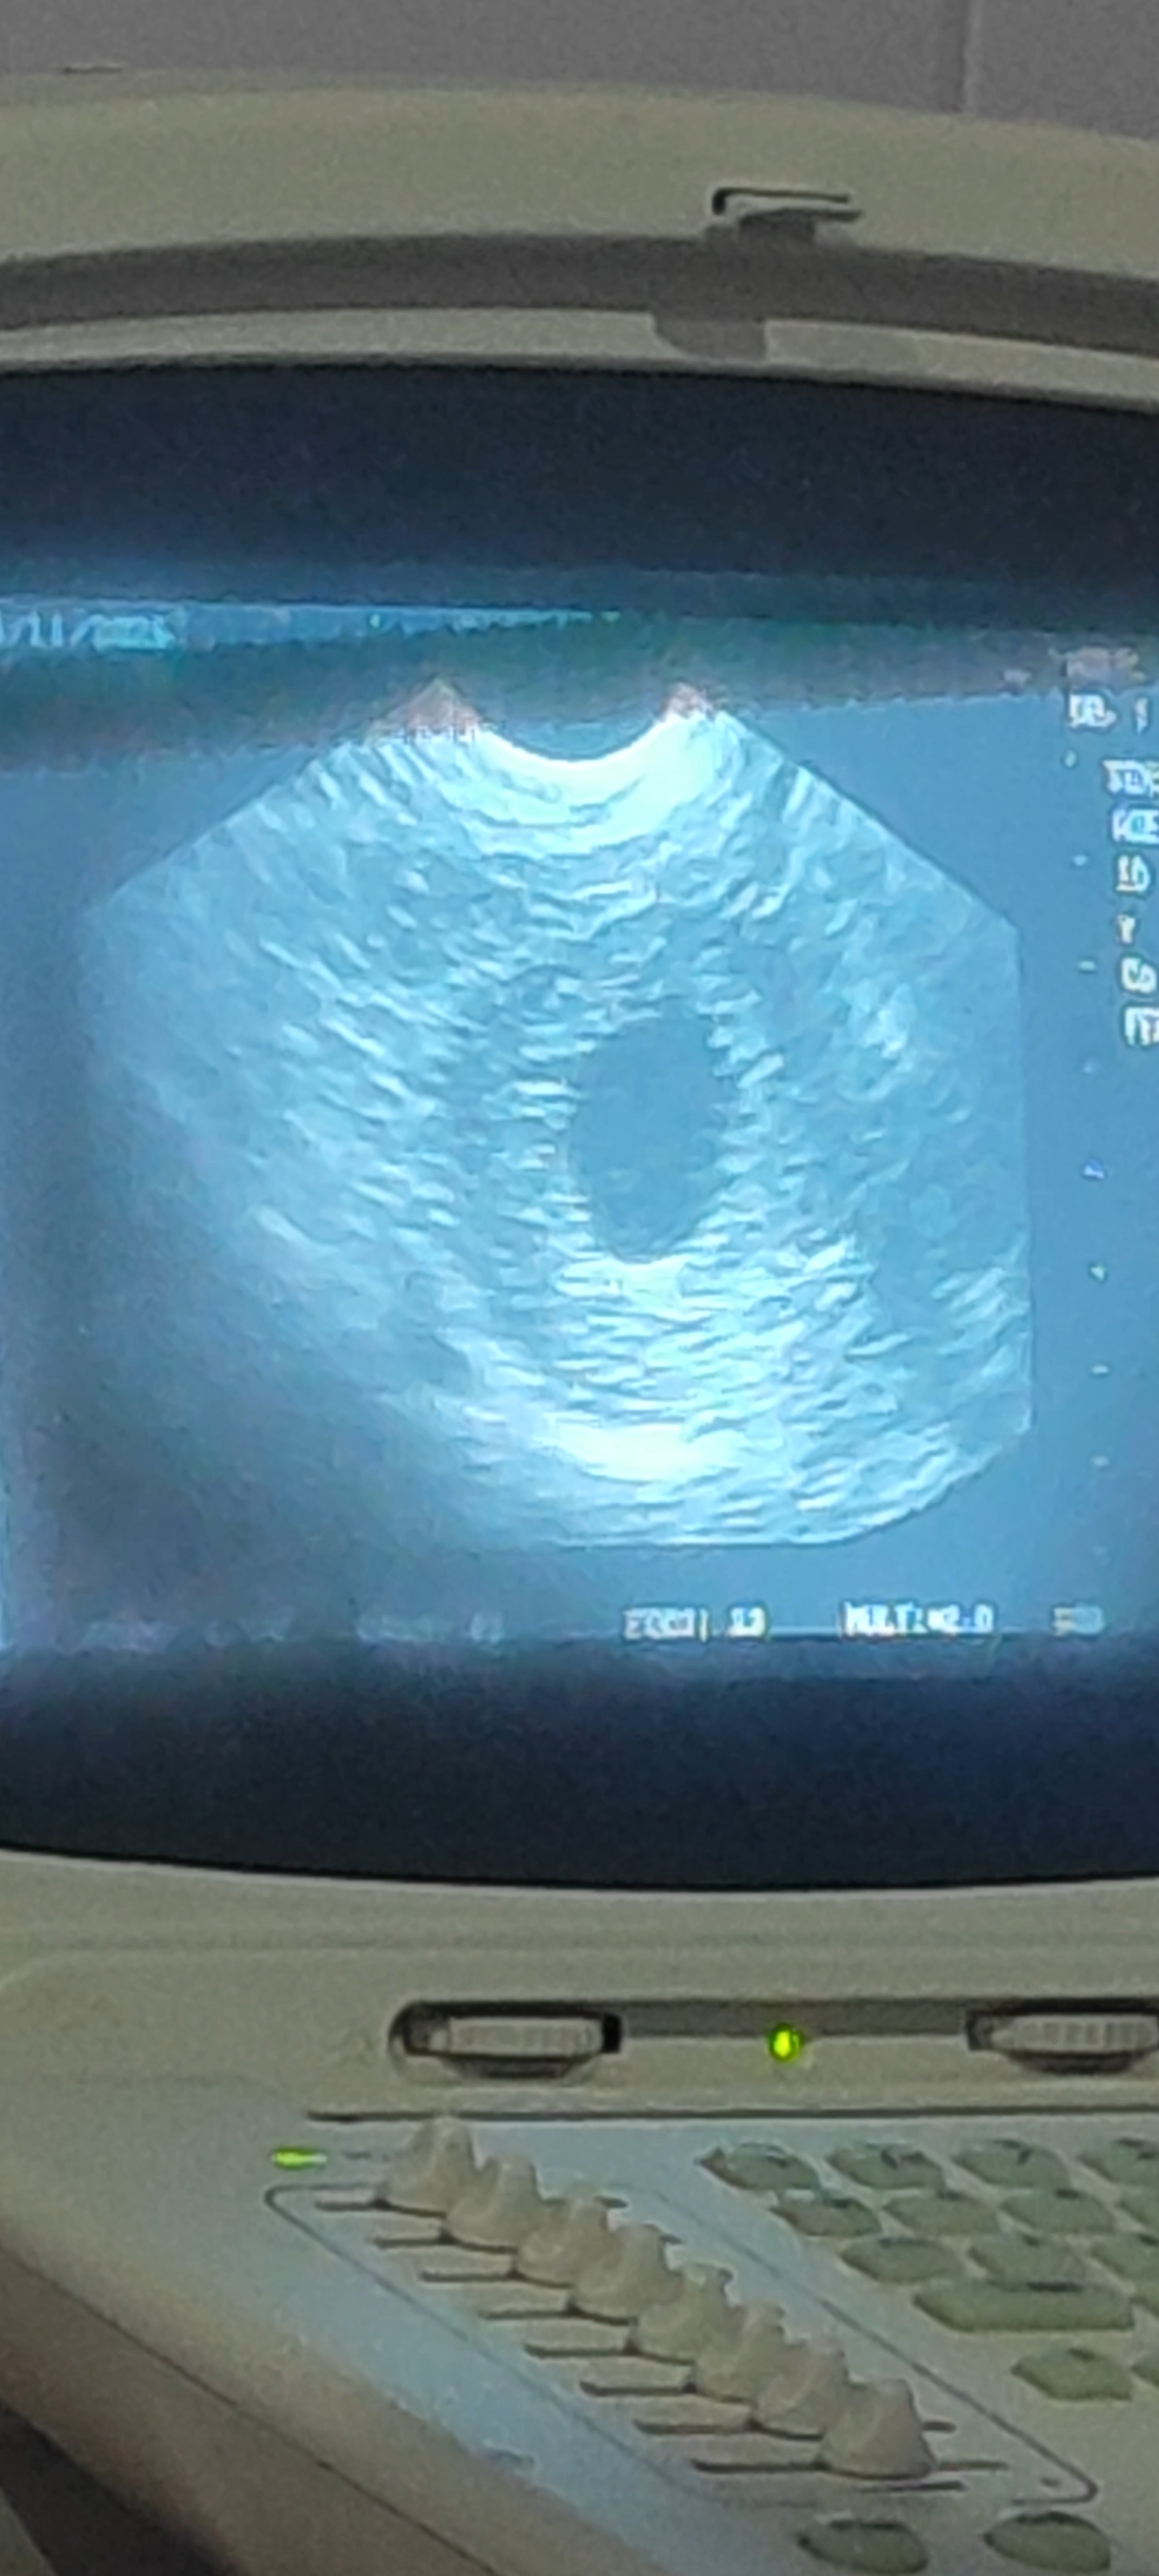

كيس حمل فارغ ولا يظهر نبض جنين ولا حتى الجنين

انا دورتي كل 29 من كل شهر واخر يوم من دورة كانت في6/2/2026 شهر ثاني يوم السادس وبعدها حدث جماع وقمت بعمل فحص حمل منزلي في 9/3/2026 شهر الثالث يوم 9 وذهبنا الى طبيت وقال يوجد حمل واليوم ذهبنا بمراجعة الطبيت يوجد كيس حمل لكن بدون جنين

هذا يعني موت الجنين ويجب التخلص منه بأسرع وقت 0 2026-04-14T10:25:03+00:00 2026-04-14T10:25:03+00:00

هذا يعني موت الجنين ويجب التخلص منه بأسرع وقت